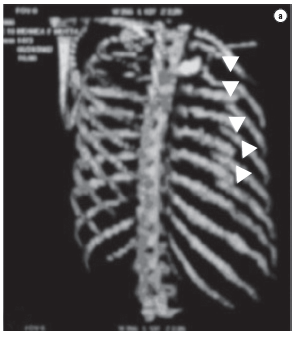

A 32-year-old female patient suffered an automobile accident which resulted in left hemopneumothorax, left pulmonary contusion and double fractures extending from the third to the eighth left costal arches, as seen on chest X-rays and computed tomography scans of the chest (Figures 1 and 2). Tomography of the skull, cervical spine, abdomen, and pelvis, were normal, as were the electrocardiogram and echocardiogram, as well as the results of tests for muscle enzymes and markers of myocardial necrosis. Water-sealed thoracic drainage was performed, and the implantation of an epidural catheter was inserted in order to provide continuous analgesia using an infusion pump. The patient presented significant chest deformation and pain, despite high doses of painkillers. It was expected that this profile, unless surgically treated, would evolve to complex deformation of the chest wall, with possible respiratory impairment. The patient did not require mechanical ventilation. In view of this clinical profile, surgical treatment was indicated in order to stabilize the fractures. The procedure was performed using left posterior lateral thoracotomy. We found double fractures extending from the third to the eighth left costal arches, with complete rupture of various intercostal pedicles, herniation, and impaction of the fractured segment (six arches) within the pleural cavity, with significant compression of the pulmonary parenchyma (traumatic thoracoplasty). We performed reduction of the fractures and fixation of the ribs with number 5 steel wires, perforating the extremities of the ribs with a nº 2 drill, passing the steel wire from one rib segment to another, and tying it. A chest tube was inserted and left in place until the third day. The patient evolved to excellent pain control and improved respiratory dynamics. Postoperative X-rays and tomography scans confirmed the favorable result of the surgical treatment (Figure 3).